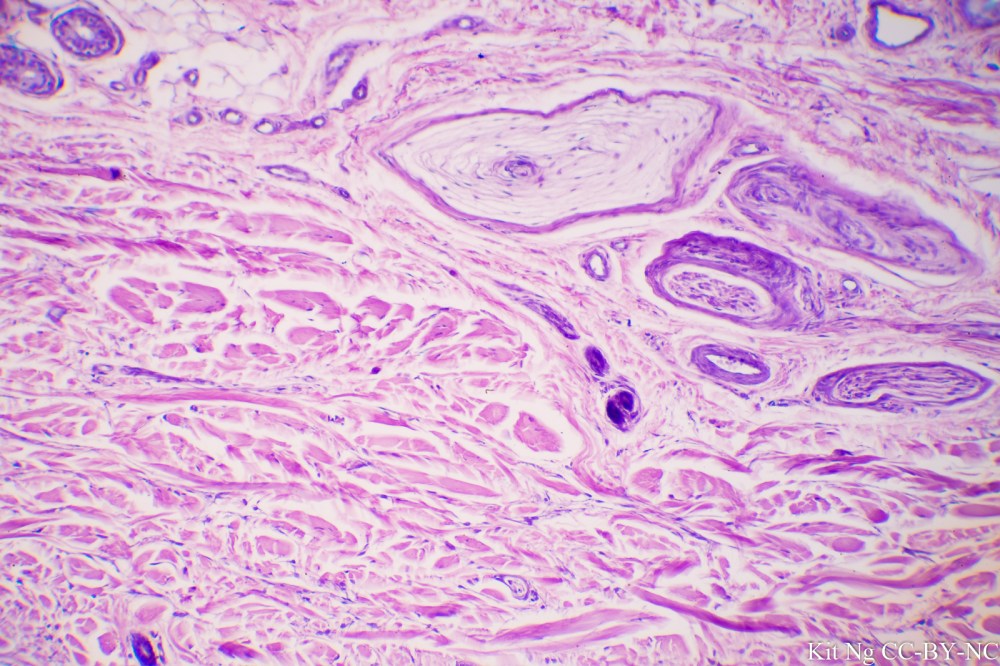

Pacinian corpusles are structures that can be found in the dermis. They are the encapsulated end of a sensory neuron that detects vibration and pressure. The corpuscle resembles a flattened plate.